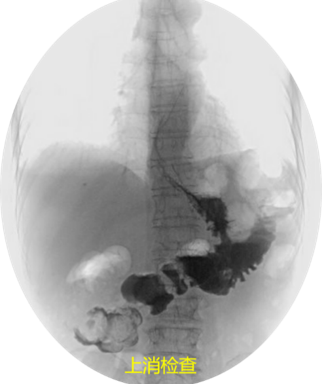

“會不會是術後內疝及腸繫膜上靜脈血栓形成導致小腸功能障礙及腹瀉?”胃外科王華攝接診後結合以往檢查結果,指出問題的關鍵。為進一步確診,透過對患者上消化道造影檢查和腹部血管CT重建後,發現造影劑直接從胃流入橫結腸,而腸繫膜上靜脈扭轉近乎閉塞。這次,終於找到了全叔的病根——胃空腸結腸瘻合併腹內疝!

目前,主要的診斷方法有消化道造影、內鏡或CT掃描,消化道造影是最靈敏的檢查手段。內鏡檢查可更直觀顯示瘻口位置及大小,但瘻口較小時會被腸壁皺褶藏匿,不易發現。治療方法則包括內鏡下封堵和手術切除瘻口並重建消化道,在國內,內鏡下治療尚未充分開展,積極的手術治療依然是目前的首選。(更多新聞資訊,請關注羊城派 pai.ycwb.com)